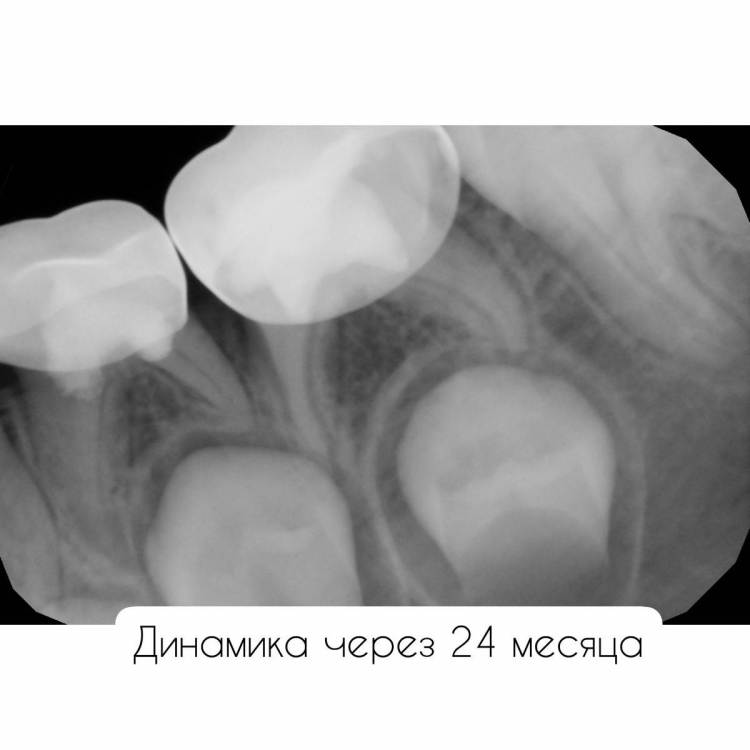

CRAZYDUCK Опубликовано 28 июня, 2022 Автор Поделиться Опубликовано 28 июня, 2022 Ладно , только по снимку нельзя установить диагноз . нет в 6.5 кариозных полостей . только нерентгенконтрастная пломба из градиа , которую я поставила двумя годами ранее . Вот оно как было ДО 3 1 Ссылка на комментарий